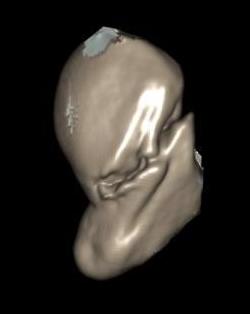

Scaphoid waist fracture 1 mm displaced

Scaphoid fracture with significant displacement

Scaphoid proximal pole fracture